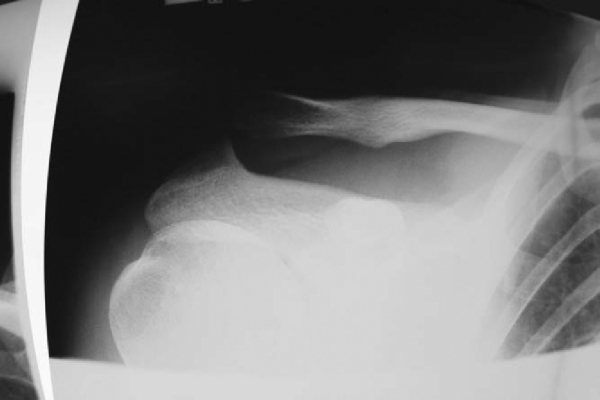

| • | Zanca view: 10- to 15-degree cephalad tilt ( Fig. 28-2 ) |

|